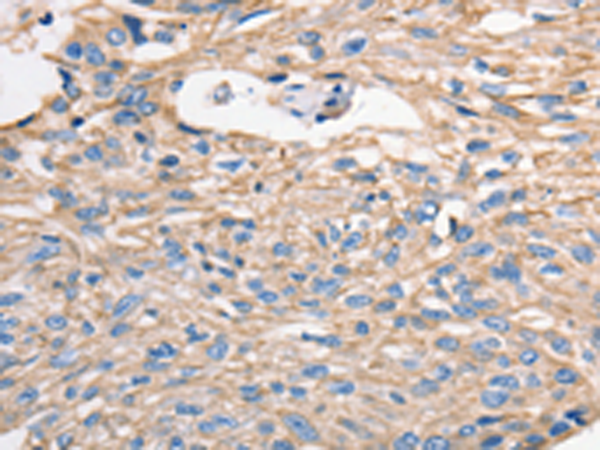

分类: 科研抗体货号: P07407别名: FLA10; KLP-20应用: WB,IHC反应种属: Human, Mouse